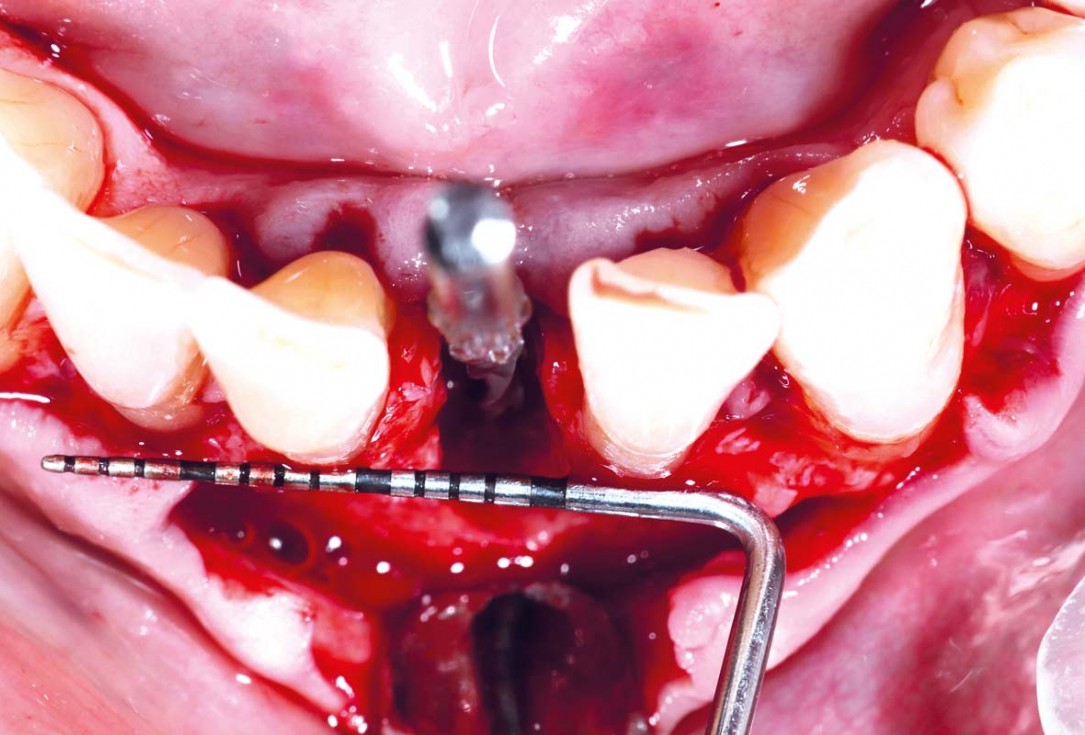

47 years old patient referred by another dentist after suffering a fall while fishing